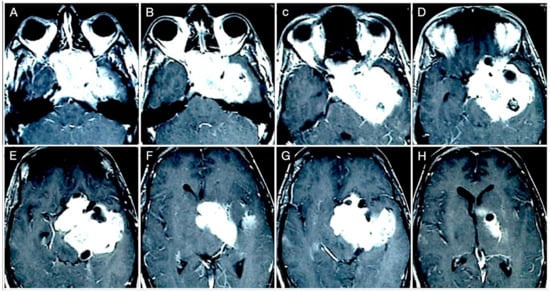

3.3.1. Case #4: Involvement of the Middle Skull Base with Parenchymal Invasion

3.3.2. Case #5: Extension beyond the Lateral Wall of the Cavernous Sinus